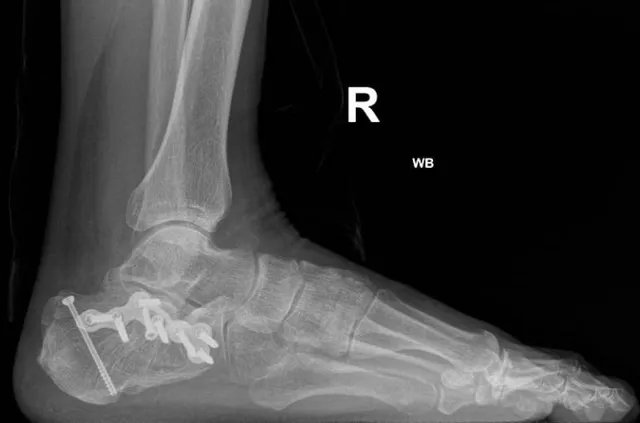

Foot and ankle conditions can significantly impact a patient’s daily life, causing pain, instability, and difficulty with basic movements. At Summit Orthopaedic Hospital, we recognize the importance of early and accurate diagnosis in effectively managing these issues. Treatment plans tailored to each patient’s specific condition—whether it involves trauma, deformity, degenerative disorders optimal recovery and a return to normal function as quickly as possible.

Some of the most common foot and ankle problems treat at our hospital include

• 1. Management of foot and ankle fractures

• 2. Lisfrancs and ankle syndesmotic injury management.

• 3. Management of flat foot, Charcot (diabetic ) foot, hallux valgus and other foot deformities.

• 4. Malunited calcaneal fractures.